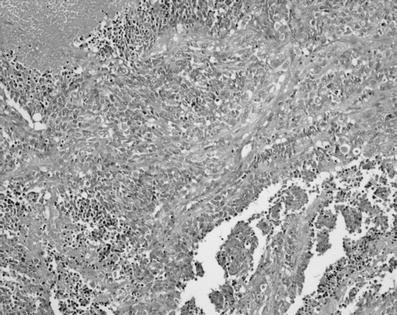

Foci of adenocarcinoma with sarcomatous component and areas of necrosis

Cystic endometriosis and areas of atypical hyperplasia

The combination of these two histotypes was found in our first patient. Carcinosarcoma, which we found in our second patient, is considered a rare variety. Both tumors are very aggressive histotypes. Nevertheless, it has been reported that endometriosis-associated ovarian cancer has a better prognosis than the non-associated one [19]. Despite that we cannot draw any conclusion, our patients are still well till now.